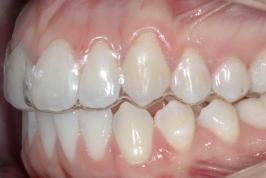

Alinhadores: o protagonismo é do paciente

07.06.2025 07h50

COLUNISTA

O segredo dos alinhadores de dentes

05.10.2024 06h24

Alinhadores: uso deve ser contínuo

10.12.2023 09h00